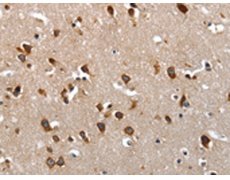

ELISA, IHC |

IHC positive control: |

Human brain and Human colon cancer |

IHC Recommend dilution: |

50-200 |